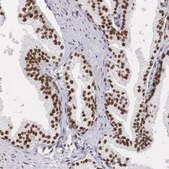

Anti-HMGN5 antibody produced in rabbit

IF, IHC

immunofluorescence: 0.25-2 μg/mL, immunohistochemistry: 1:500-1:1000

All Prestige Antibodies Powered by Atlas Antibodies are developed and validated by the Human Protein Atlas (HPA) project and as a result, are supported by the most extensive characterization in the industry.

The Human Protein Atlas project can be subdivided into three efforts: Human Tissue Atlas, Cancer Atlas, and Human Cell Atlas. The antibodies that have been generated in support of the Tissue and Cancer Atlas projects have been tested by immunohistochemistry against hundreds of normal and disease tissues and through the recent efforts of the Human Cell Atlas project, many have been characterized by immunofluorescence to map the human proteome not only at the tissue level but now at the subcellular level. These images and the collection of this vast data set can be viewed on the Human Protein Atlas (HPA) site by clicking on the Image Gallery link. We also provide Prestige Antibodies® protocols and other useful information.

• IHC tissue array of 44 normal human tissues and 20 of the most common cancer type tissues.